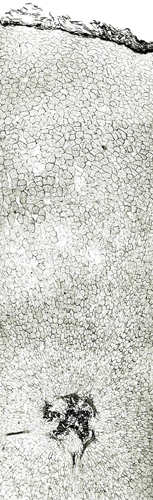

内部形態:鏡検

本品はほぼ偏球形を呈し、径1~2cmで、一端に茎の跡がある。外面は灰黄色~灰褐色で質は堅く、破砕面は黄色で平滑または灰黄緑色で粒状である。 本品はほとんどにおいがなく、味は苦い。 Corydalis属は、39節、約428種が広く世界に分布するといわれ、このうち38節,約288種が中国に分布している。このうち塊茎をつくるものは4節であり、分布が局地に限られるものを除くと、Sect. Duplotuberと Sect. Pes-gallinaceus の2つの節に限られる。Sect. Duplotuber にはチョウセンエンゴサク C. ternata (Nakai) Nakai (C. nakaii Ishidoya) および、ジロボウエンゴサク C. decumbens (Thunb.) Persが含まれる。Sect. Pesgallinaceusには C. yanhusuo Wang ex Su et Wu (C. turtschaninovii Besser forma yanhusuo Y. H. Chou et C. C. Hsu)が含まれるとされている。 |

内部形態の比較(市場品)

浙江省産市場品の横切面では、形成層は明瞭で環状につながっている。道管は形成層の近くに散在しており、中央に髄がある。コルク層を表面視するとコルク細胞は厚膜の長条形である。 韓国産市場品の横切面では、維管束が放射状に配列し、形成層は不明瞭で放射組織によって分断され、環状につながらない。コルク層を表面視すると、コルク細胞は薄膜の多角形である。

| ○延胡索 甲級 <中国浙江省> |

○延胡索 乙級 <中国浙江省>・上部 |

○延胡索 <韓国> |

兵庫県柏原における試験栽培品(浙江省産を種付け)は浙江省市場品と同様の形態を呈していた。 <横切面> ・形成層は明瞭で環状につながる。 ・道管は形成層の近くに散在している。 ・中央に髄がある。